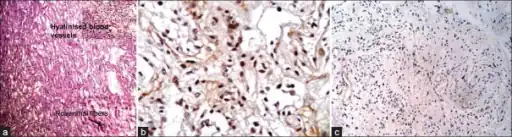

Microscopic appearance

Pilocytic astrocytomas are often cystic tumors, and, if solid, tend to be well-circumscribed.

Under the microscope, the tumor is seen to be composed of bipolar cells with long "hair-like" GFAP-positive processes, giving the designation "pilocytic" (that is, made up of cells that look like fibers when viewed under a microscope[6]). Some pilocytic astrocytomas may be more fibrillary and dense in composition. The presence of Rosenthal fibers,[7] eosinophilic granular bodies, and microcysts can often be seen. Myxoid foci and oligodendroglioma-like cells may also be present, though these are not specific to pilocytic astrocytoma. Long-standing lesions may show hemosiderin-laden macrophages and calcifications.